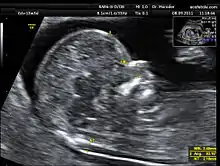

فحص قفوي

قياس الشفافية القفوي هو استخدام الأشعة فوق الصوتية أثناء فترة الحمل و قبل الولادة، بهدف التنبؤ بأمراض اختلالات الكروموسومات وتحديدًا متلازمة داون في الجنين.[1] وتخضع السيدات الحوامل بشكل اختياري لهذه الاختبار، وخاصة النساء المتقدمات في السن وذلك لارتفاع احتمالية إصابة أجنتهم بمتلازمة داون. كما قد تساعد نتيجة المسح على التنبؤ بوجود تشوهات خلقية بقلب الجنين.

ويتم إجراء هذا المسح في الفترة ما بين 11-13 أسبوع من الحمل وهي الفترة التي تكون فيها قاعدة عنق الجنين لازالت شفافة. فيتم تقييم كمية السائل الموجود في القسم الخلفي لعنق الجنين، ومن هنا جاء اسم الفحص "قياس الشفافية القفوي". ولا يمكن إجراء هذا المسح بعد مرور 13 أسبوع و6 أيام من الحمل.[2]

يستغرق فحص قياس الشفافية القفوي حوالي 15 - 20 دقيقة . تستلقي المراة الحامل على كرسي مائل إلى الخلف، تماما كما في اختبار الموجات فوق الصوتية المعتاد. يوضع المسبار على بطن المرأة وتحديدًا في موقع الرحم والجنين، فيتمكن الطبيب من رؤية صورة الجنين على الشاشة الموضحة. عندما يكون الجنين مستلقيا على جنبه. وبطريقة معينة يتم قياس حجم الجنين و قياس سُمك السائل الموجود في قاعدة عنق الجنين بين الجلد وما تحته، و هو السائل العنقي اللمفاوي، ويوجد هذا السائل بكميات محددة في الأجنة الطبيعية.[3] أما في الحالات التي يكون فيها الجنين مصابًا بأمراض تتعلق بالجهاز العصبي واختلال الكروموسومات يتواجد هذ السائل بكميات كبيرة نسبة لحجم الجنين.